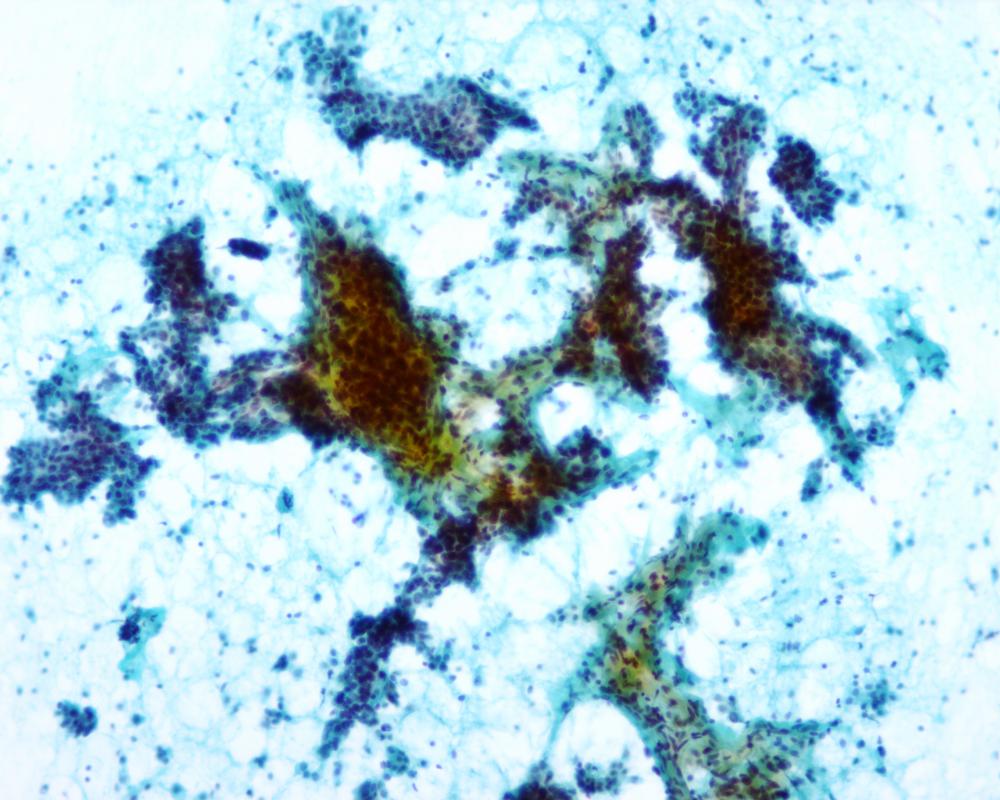

第37回日本臨床細胞学会九州連合会学会(佐賀)スライドカンファレンス症例4

種別:泌尿器

出題:○松山 篤二 福岡和白病院病理診断科

| 年齢 | 68歳 | 性別 | 男性 |

| 採取部位 | 尿 | 採取方法 | 自然尿 |

| 検体処理法 | 従来法 |

既往歴:大腸癌

現病歴:S状結腸癌ならびに肺転移にて化学療法中。2週間前から排尿困難、残尿感があり、泌尿器科に紹介された。直腸診で前立腺は超胡桃大、全体に固く表面やや不整であった。精査のため、まず尿細胞診が行われた。

(画像2、5~8は同一の倍率です)

| 正解 | 1.大腸癌 |

| 1.大腸癌 | 3件 | (3.8%) | |

|---|---|---|---|

| 2.前立腺癌 | 44件 | (55.0%) | |

| 3.高異型度尿路上皮癌 | 17件 | (21.2%) | |

| 4.低異型度尿路上皮癌 | 8件 | (10.0%) | |

| 5.反応性尿路上皮 | 8件 | (10.0%) | |

| 投票総数 | 80件 | (100%) |